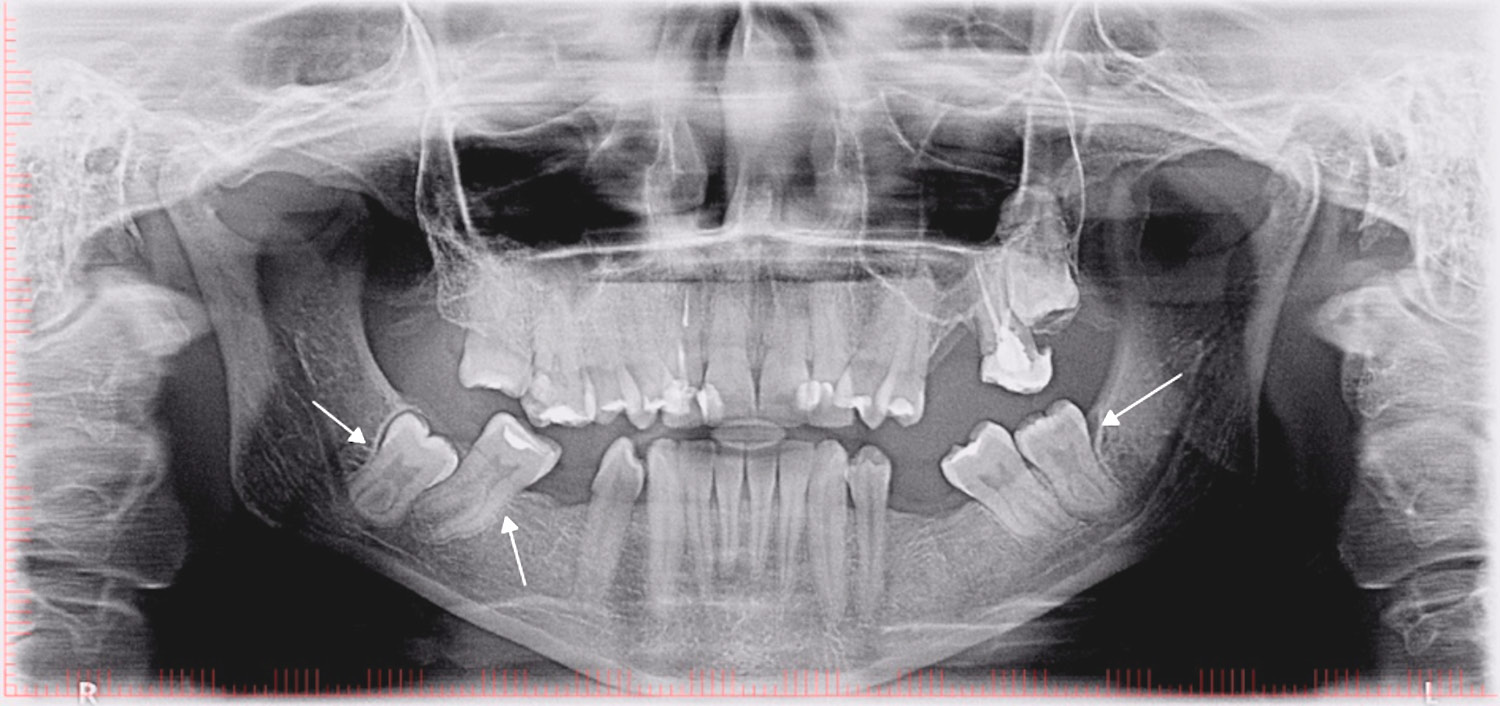

A taurodont tooth is characterized by an apical displacement of the pulpal floor and shortening of the roots. A lack of constriction at the cementoenamel junction (CEJ) is a characteristic feature.3 On clinical examination, a taurodont tooth is not visibly different from the other teeth, as this anomaly is only detected on radiographic imaging.

The endodontic treatment of taurodont teeth is complex and difficult because of the apical displacements of the pulpal chamber floor, which makes it harder to find the localization of the root canals.5, 6, 11, 15, 16 Taurodont teeth often have an incorrect configuration of the root canal system and additional canals (Figure 2, Figure 3). Increased bleeding during pulp chamber trepanation may be mistaken for perforation1; however, due to root shortening and the apical displacement of the pulpal chamber, floor perforations can occur.3, 12, 17 The complexity of the root canal system makes its instrumentation almost impossible. Because of this, the authors recommend the use of sodium hypochlorite to dissolve the remaining pulp that cannot be removed with instruments.13, 18 Kulkarni et al. described a case of a patient who underwent root canal irrigation of tooth 37 with 2.5% sodium hypochlorite, 17% aqueous ethylene diamine tetra-acetic acid (EDTA) solution, 2% chlorhexidine gluconate, and saline.4 According to Bharti et al., an irrigation with 5% sodium hypochlorite for 20 min–2 h can completely dissolve the pulp.19 However, Prakash et al. recommended the irrigation with sodium hypochlorite be limited to single-use to minimize the detrimental effects in the periapical tissues.8

With regard to dental surgery, it should be taken into account that the extraction of a taurodont tooth may be more difficult because of the apical shift of the furcation, the root apical area being shorter and thinner,5, 16 and the roots having a widened dimension in the 1/3 of their length (Figure 2).3, 5, 17 Paradoxically, due to their large crown and short roots, such teeth are less seated in the alveolus, and thus may be easier to extract than their cynodont counterparts.1, 2, 15

There are several ways to diagnose taurodontism. In 1928, Shaw classified the subtypes of this disease as hypo-, meso- and hypertaurodontism, based on the relative shift of the pulpal floor. This subjective assessment has often led to a misdiagnosis of this anomaly.4 In 1978, Shifman and Chanannel (Figure 4), and later Kim Seow and Lai (Figure 5), developed taurodontal indices in order to determine the occurrence of taurodontism and classify it based on a biometric study, as shown radiographically (Figure 2, Figure 3).3 Determining taurodontism consists of dividing the distance between the lowest point of the pulp chamber roof and the highest point of the pulpal floor by the distance between the lowest point of the pulp chamber roof and the apex, and then multiplying the result by 100. When this value is equal to or greater than 20, the patient is said to have a taurodont tooth. Values from 20 to 29.9 classify the tooth as a hypotaurodont, values from 30 to 39.9 classify it as a mesotaurodont, and values from 40 to 75 identify it as a hypertaurodont. The 2nd index used to identify taurodontism calculates the crown-to-root ratio of the tooth. This is accomplished by measuring the distance from the deeper furrow on the occlusal surface of the furcation and comparing it to the distance from the furcation to the apex. A result from 1.1 to 1.29 indicates hypotaurodontism, from 1.3 to 2.0 indicates mesotaurodontism and above 2.0 indicates hypertaurodontism.3, 13